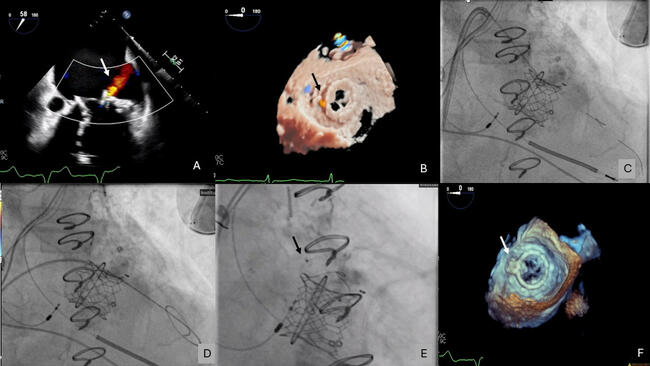

Video 1. Transesophageal echocardiogram demonstrating mitral paravalvular leak originating laterally between the transcatheter valve and surgical ring.

Video 2. Fluoroscopy images demonstrating the presence of the Confida wire (Medtronic) across the defect and in the left ventricle.

Video 3. Fluoroscopy images demonstrating release of the 6 x 6-mm Amplatzer Ductal Occluder II (Abbott).